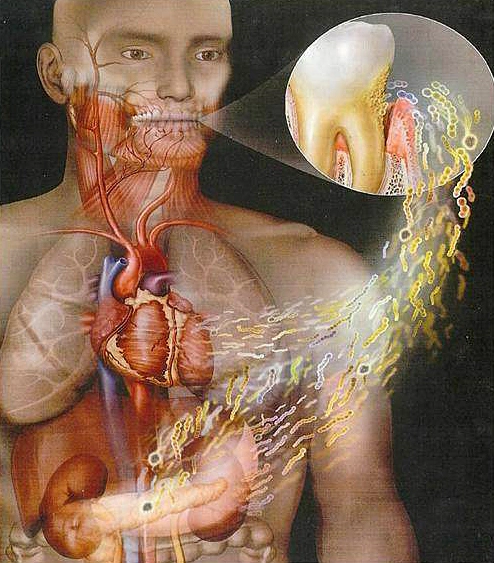

How Can Poor Oral Health Affect the Rest of the Body?

Oral health is extremely important for many reasons. If patients suffer from gum disease, cavities, or bad breath this can cause issues with your teeth and mouth. Our mouths are a pathway for bacteria to enter the body. The bacteria are able to enter the blood stream, and this can also cause infection or inflammation in other parts of our

New Studies Amplify the Health Risks Associated with Periodontal Disease and the Benefits of Treatment.

At the October 2011 American Heart Association scientific sessions in Orlando, two very large studies amplified the increased risk of heart attack and stroke caused by deep periodontal pockets and bleeding – as well as pointing out the benefits of having your teeth professionally cleaned to reduce these risks. In the first study, 7999 patients with periodontal disease in Sweden